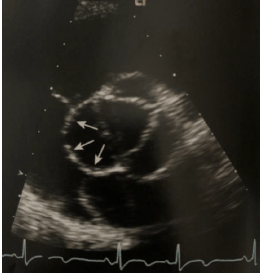

Paciente de 18 anos de idade com queixa de cansaço leve aos esforços veio para a realização de ecocardiograma transtorácico de rotina. Ao exame, apresentou dilatação do seio coronário com o restante do exame dentro da normalidade. De acordo com a patologia suspeita, analise as afirmativas abaixo e dê valores verdadeiro (V) ou falso (F).

( ) A Veia cava superior esquerda persistente (VCSEP) é uma anormalidade causada pela persistência da veia cardinal inferior esquerda

( ) Uma VCSEP pode ser confirmada por meio da injeção de contraste de solução salina no sistema venoso da extremidade superior esquerda do paciente

( ) Em 90% dos pacientes portadores de VCSEP, esta desemboca no átrio esquerdo enquanto que os 10% restantes drenam diretamente para o átrio direito

( ) Mesmo quando patologia isolada, apresenta-se hemodinamicamente significativa.